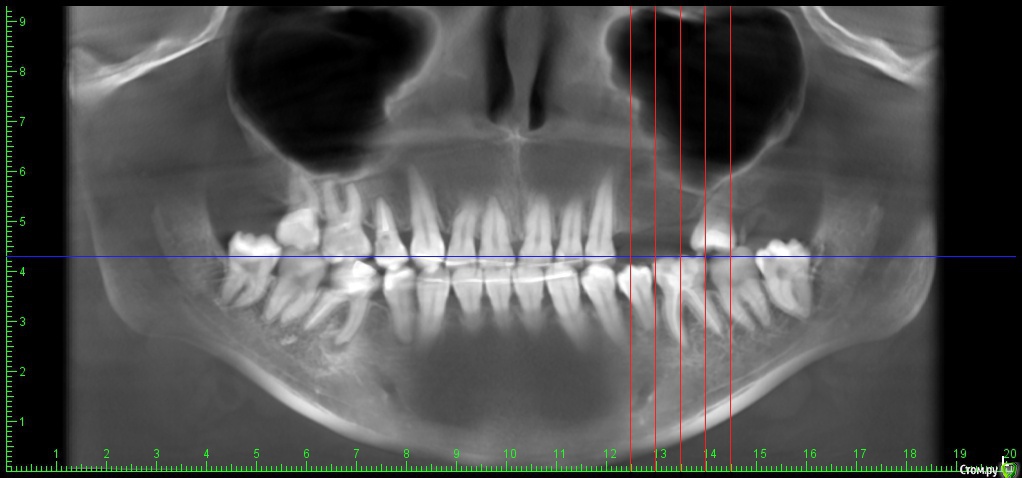

DenisV Опубликовано 12 мая, 2018 Поделиться Опубликовано 12 мая, 2018 (изменено) Уважаемые коллеги помогите начинающему имплантологу, в области 2.6 ЗСЛ, в области 2.4 как лучше поступить? расщепление + сст, или НКР? Изменено 12 мая, 2018 пользователем DenisV Ссылка на комментарий

DenisV Опубликовано 12 мая, 2018 Автор Поделиться Опубликовано 12 мая, 2018 ширина гребня в области 2.4 - 4мм Ссылка на комментарий